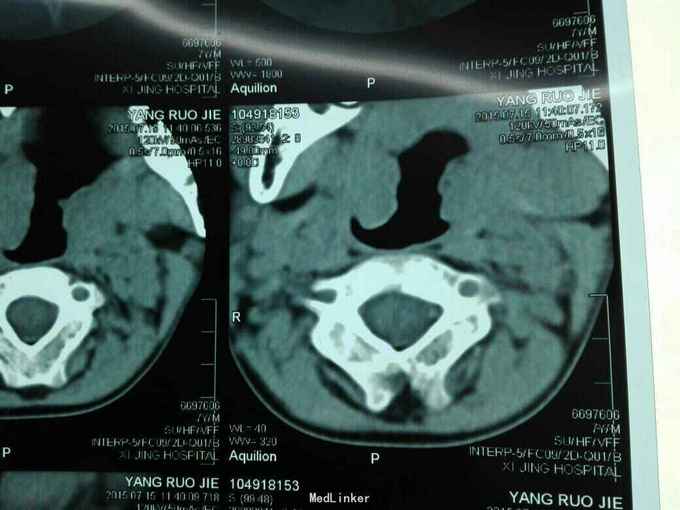

先天脊柱畸形

先天脊柱畸形8年。